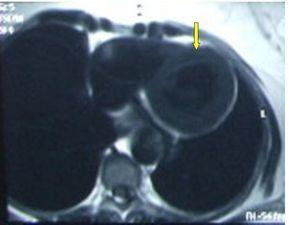

En las pruebas complementarias realizadas destacaba un EKG con trazado en ritmo sinusal con registro electrocardiográfico compatible con hipertrofia de ventrículo izquierdo. Radiografía de Tórax (figura 1) con calcificación del botón aórtico, con imagen indicativa de aneurisma de aorta torácica. Aparato urinario en vacío: se visualizan de forma completa las dos siluetas renales. No se visualizan calcificaciones vasculares. Ecocardiografía: compatible con hipertrofia moderada del ventrículo izquierdo. Ecografía Doppler renal: se observan ambos riñones de configuración normal, riñón derecho de 10,3 cm y riñón izquierdo de 9,4 cm de tamaño, con ecoestructura compatible con la normalidad. Índices de resistencia normales. Imagen ecográfica de dudoso aneurisma tóraco-abdominal.

Debido a los hallazgos radiológicos de aneurisma y asimetría renal leve, solicitamos una angio-TC torácica en la que se evidencia un aneurisma de aorta descendente distal, de tipo sacular, de 4,3 cm de diámetro. Ampliamos estudio con una angio-IRM toráco-abdominal (figura 2, figura 3, figura 4, figura 5) en la que se observan signos de miocarditis. Estenosis en múltiples niveles de la aorta, con signos de inflamación activa y aneurisma focal de aorta torácica descendente. Afectación difusa de aorta abdominal, así como de sus principales ramas viscerales. Triple arteria renal derecha y doble arteria renal izquierda. Estenosis de la arteria polar superior izquierda.

Figura 2. Angio-IRM cardíaca.